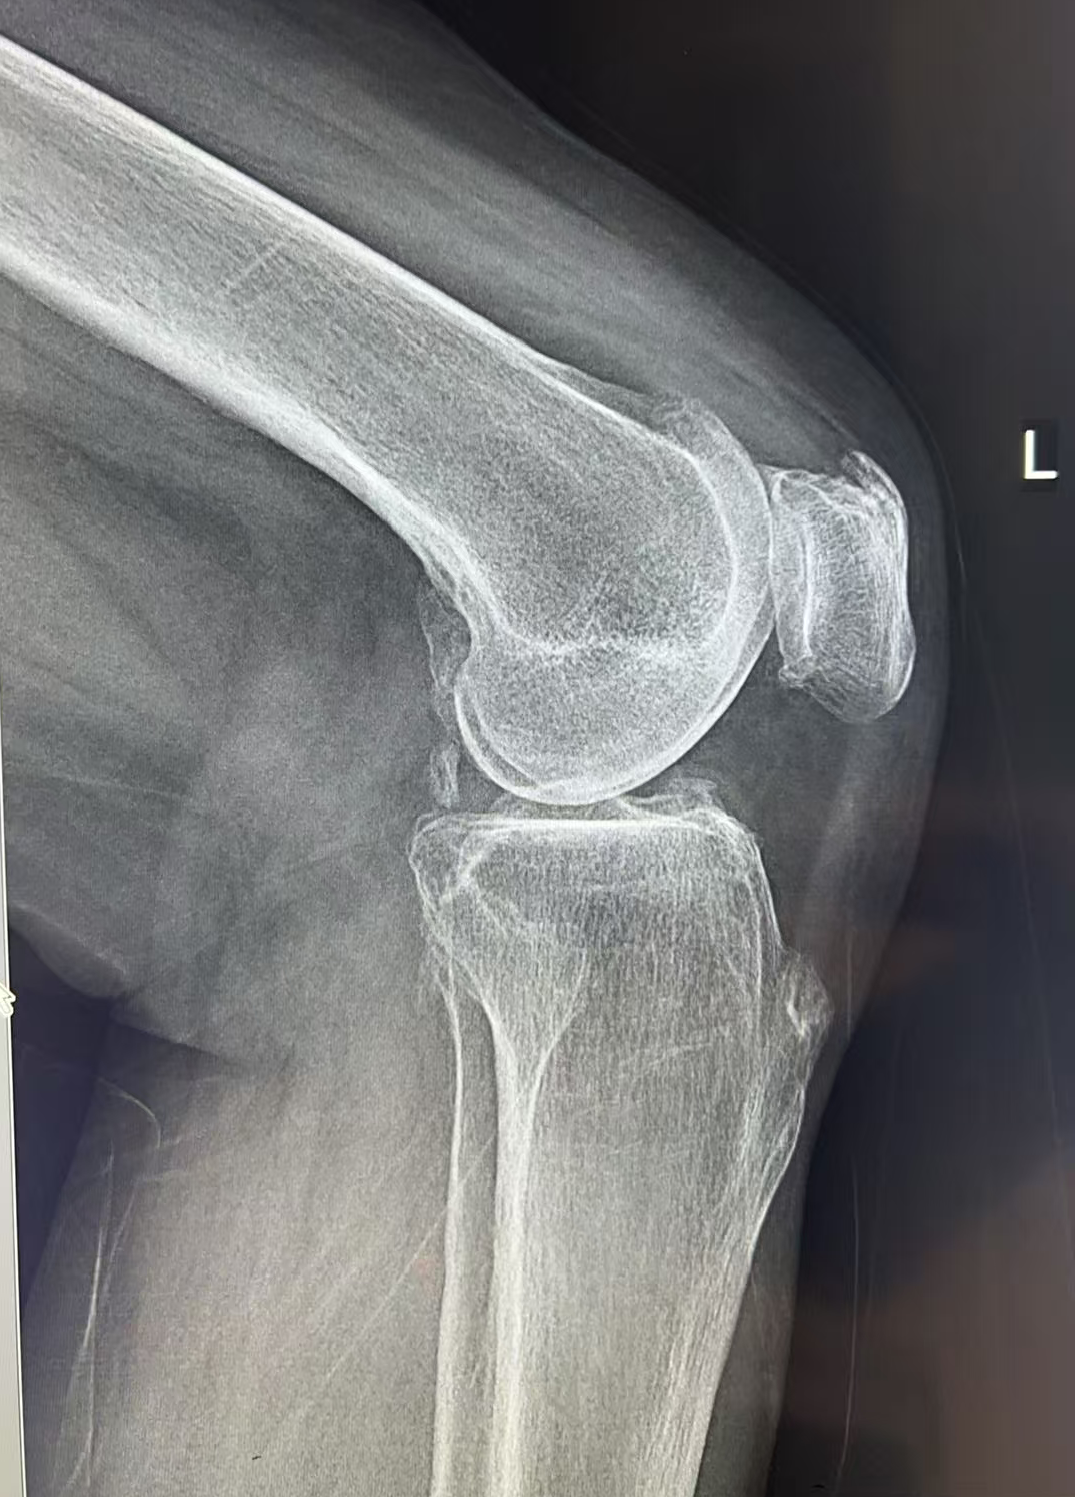

接诊她的是王歆峰主任,王主任耐心地听王阿婆讲了自己的情况,又仔细给她做了查体,还安排了详细的检查。最后确诊,王阿婆得的是“左膝关节骨性关节炎”。

经过仔细评估,王歆峰主任决定给王阿婆做“左膝内侧单髁表面置换术”!这就是保膝治疗的一种,简单说,就是只修复膝盖磨损的那一部分,不用把整个膝盖关节换掉,创伤小、恢复快,还能保留膝盖原本的功能。

像王阿婆这样的中老年人,膝盖疼反反复复,确诊为膝关节骨性关节炎,而且磨损主要集中在膝盖的一侧,没有严重的畸形,大多都适合保膝治疗。当然,具体能不能做,还得医生经过详细检查和评估后才能确定。